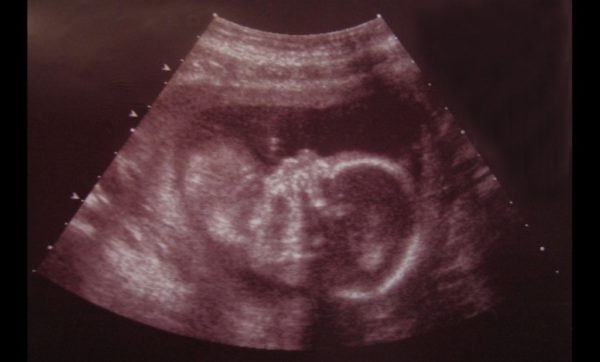

«Φυσικά, αυτή η μαρτυρία υπέρ της ζωής και του ερχομού στον κόσμο ενός ήδη συλληφθέντος ατόμου θα έχει πραγματικά σημασία μόνο όταν όσοι αντιμετωπίζουν αυτό το σοβαρό πρόβλημα καταλάβουν ότι το έμβρυο είναι ένας άνθρωπος προικισμένος με ταυτότητα και αξιοπρέπεια. Αν και δεν βλέπουμε το έμβρυο, το πρόσωπό του θυμίζει τη θεία εντολή: «Ου Φονεύσεις!» δήλωσε ο κ. Μπανέσκου.